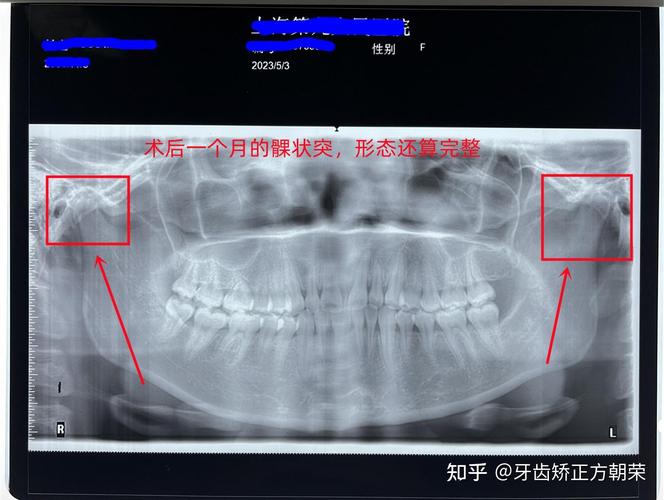

下颌骨全景片(曲面断层片,Orthopantomogram, OPG)

- 原理: 患者站立或坐着,下颌置于旋转架的托板上,X线管和探测器(胶片或数字探测器)围绕患者头颅做同步旋转,获得下颌骨、上下颌牙列及部分颞下颌关节的连续、全景影像。

- 观察整个下颌骨(体部、升支、髁突、喙突)的整体形态、连续性。

- 观察颞下颌关节的大致位置和形态(但不如专用关节片清晰)。

- 存在影像变形、放大和重叠(尤其是升支后部和髁突区域)。

- 对骨皮质细微骨折、关节间隙、关节盘等软结构显示不清。